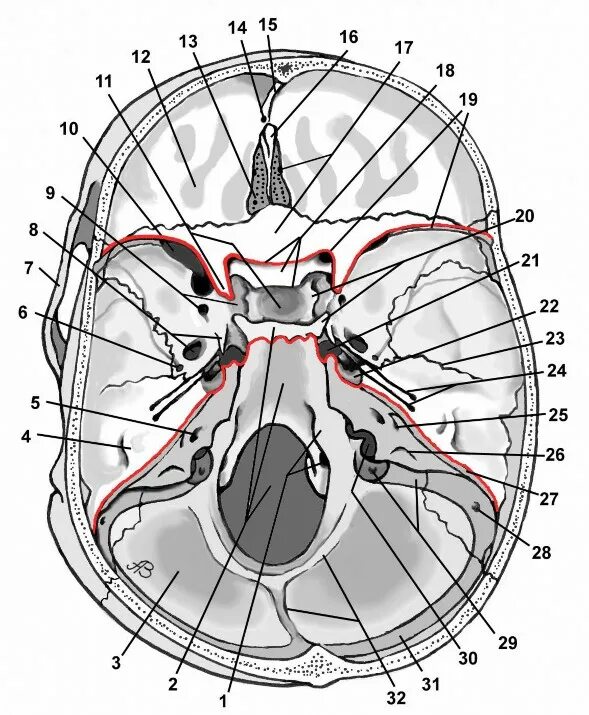

Спинка турецкого седла